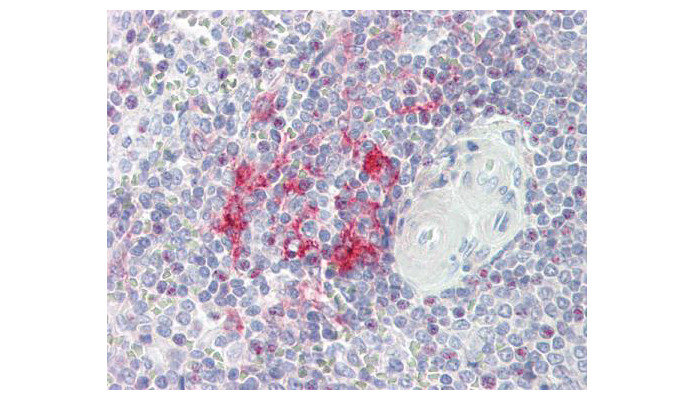

- Experimental details

- LITAF antibody [N1C3] detects LITAF protein at cytoplasm on placenta by immunohistochemical analysis. Sample: Paraffin-embedded placenta. LITAF antibody [N1C3] (OAGA00745) dilution: 1:100.